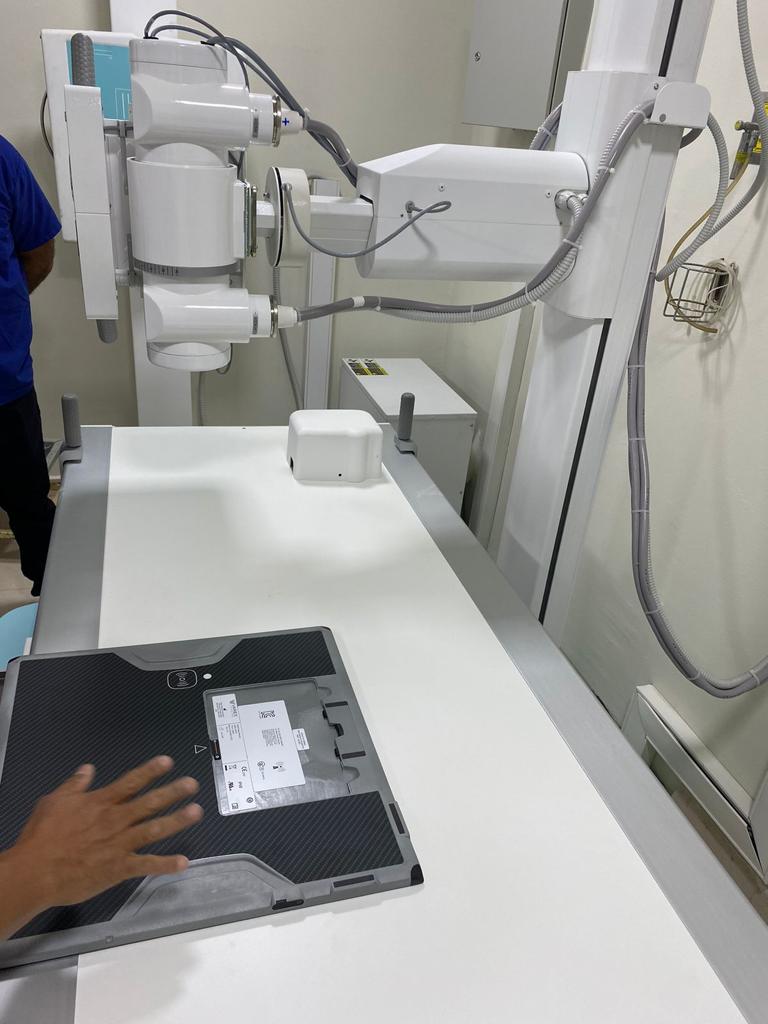

San Juan Bautista Tuxtepec, Oax., 23 de octubre de 2023.- El Hospital General de San Juan Bautista Tuxtepec de los Servicios de Salud de Oaxaca (SSO) cuenta ahora con una Unidad Radiológica Digital para estudios de Tórax que cubrirá las necesidades en operatividad de las áreas de traumatología, urgencias, exámenes estándares y especializados.

Este equipo moderno y de alta tecnología que requirió una inversión de más de tres millones de pesos, facilitará y acortará los tiempos de espera para el diagnóstico de distintas enfermedades en las y los pacientes que diariamente se atienden en este nosocomio.

Después de siete años que no se contaba con este equipo tan necesario para cubrir estas necesidades, el Hospital General de San Juan Bautista tendrá ahora una productividad mínima de 40 placas por hora.